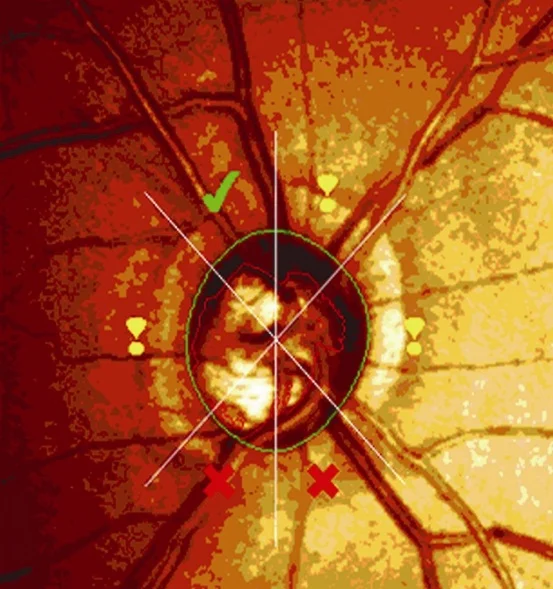

Confocal scanning laser ophthalmoscopy

-